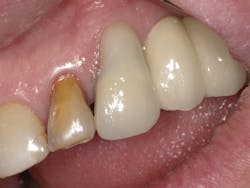

Case Three is a challenging crown repair on a medically compromised patient. The preoperative image shows decay at the buccal margin of an anterior abutment to a bridge (figure 11). Following excavation with the Lite Touch laser (figure 12), we decided to use Futurabond U in a self-etch technique followed by layering Admira Fusion in two increments. The first increment was an opaque layer, using shade OA2 to attempt to block out the gray margin of the porcelain-fused-to-metal crown (figure 13). After light-curing that layer, we applied shade A1 and light-cured and polished the restoration, achieving a highly esthetic result given the difficulty of the situation (figure 14).

Figure 13

Figure 14